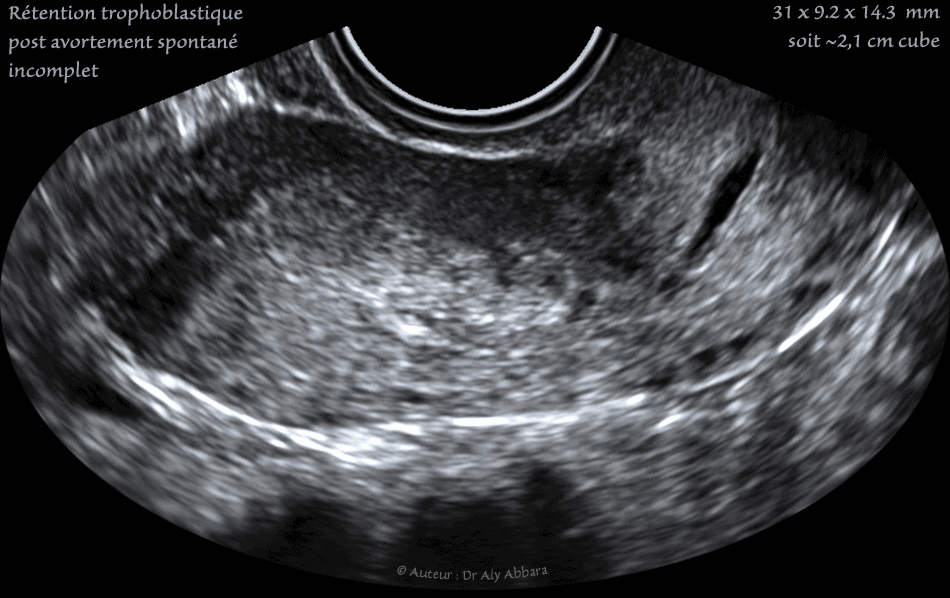

• Images échographiques montrant (sur des coupes sagittale, transverse et frontale) la présence d'une rétention trophoblastique mesurant environ 31 x 9.2 x 14.3 mm (soit 2,6 cm3).

La cavité utérine est occupée par une masse oblongue hétéroéchogène à contour irrégulier.

L'endomètre sur ces images est difficilement identifiable.